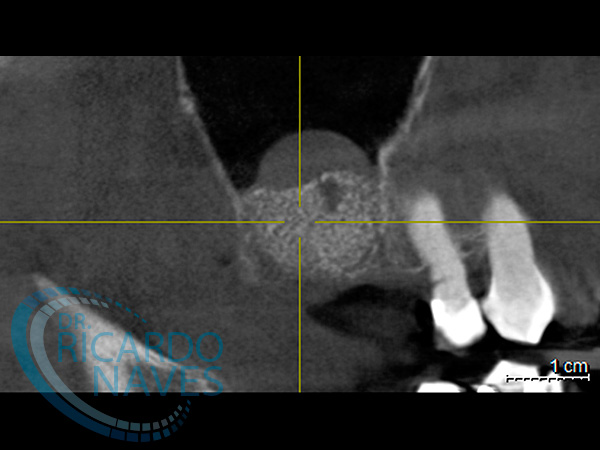

Elevación de seno maxilar técnica de ventana lateral.

Antes y después de elevación de seno bilateral. 5 meses de evolución. Obsérvese la cantidad de hueso que podemos ganar  en estas verdaderas cajas biológicas.